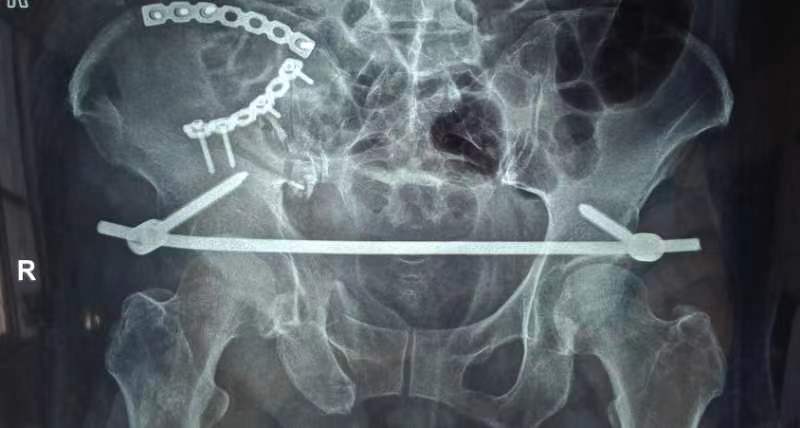

“通常情况下,我们会选择骨盆骨折切开复位内固定术或支架外固定术。不过,这些方法都存在一定问题。钢板内固定术创伤较大,出血多,手术时间长,风险也相对较高。而支架外固定术则会影响患者的日常活动,特别是翻身或坐下时的不适感。”科主任程福宏说到。

由于患者骨盆旋转和垂直不稳定,以及严重失血和肥胖,骨一科医疗团队进行讨论分析,决定采用微创内固定手术。8月25日成功完成手术,术后第二天患者能够在床上半靠,翻身时疼痛明显缓解,下肢功能恢复良好。

Infix(骨盆内固定支架)技术是一种最新的微创内固定方法,适用于治疗不稳定型骨盆前环损伤,尤其适合肥胖、腹部有手术刀口、体弱或有膀胱造瘘患者。该技术融合了内固定和外固定优点,通过透视下的精准操作和微创置钉,实现了骨盆环的稳定,使患者能够进行早期功能锻炼,最大程度降低了伤致残的风险。